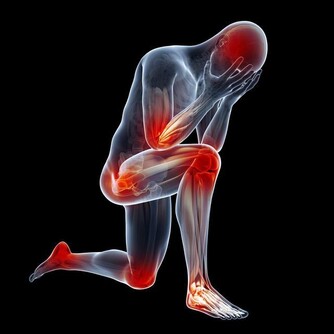

血栓是全身性的疾病,症狀有多種,有的卻很不明顯,往往讓人忽略或者會聯想到其他方面的疾病,比如肢體發涼、腫脹、頭暈、呼吸困難等,都可能與血栓有關聯。

三、肢體麻木

許多血栓患者在開始時表現出不同程度的麻木感。你可能會以為是壓到了或者是累著了,直到發展為疼痛才會想到就醫。但其實這可能是由於心臟或者其他部位的血栓進入了你的動脈。

腿動脈栓塞以後,這部分腿部就會缺血,變得皮膚蒼白、溫度降低,甚至連足背動脈都可能摸不到了。